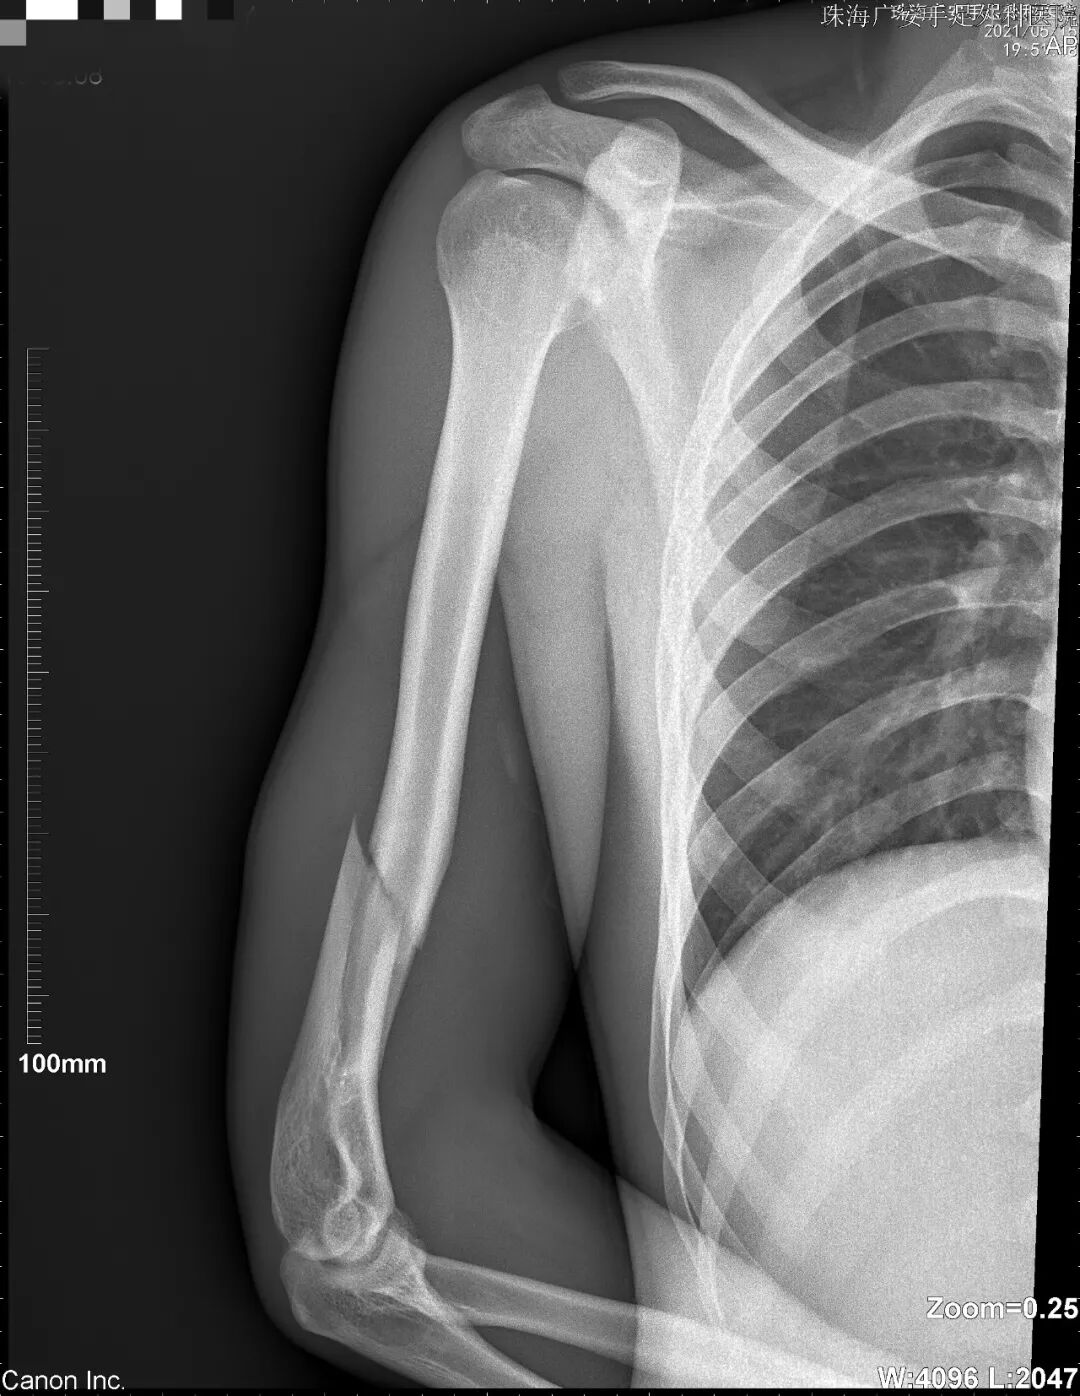

后来到我院就诊时,姜先生右上臂肿胀、压痛明显,急诊X线显示其右肱骨骨折,住院接受右肱骨骨折切开复位内固定术。